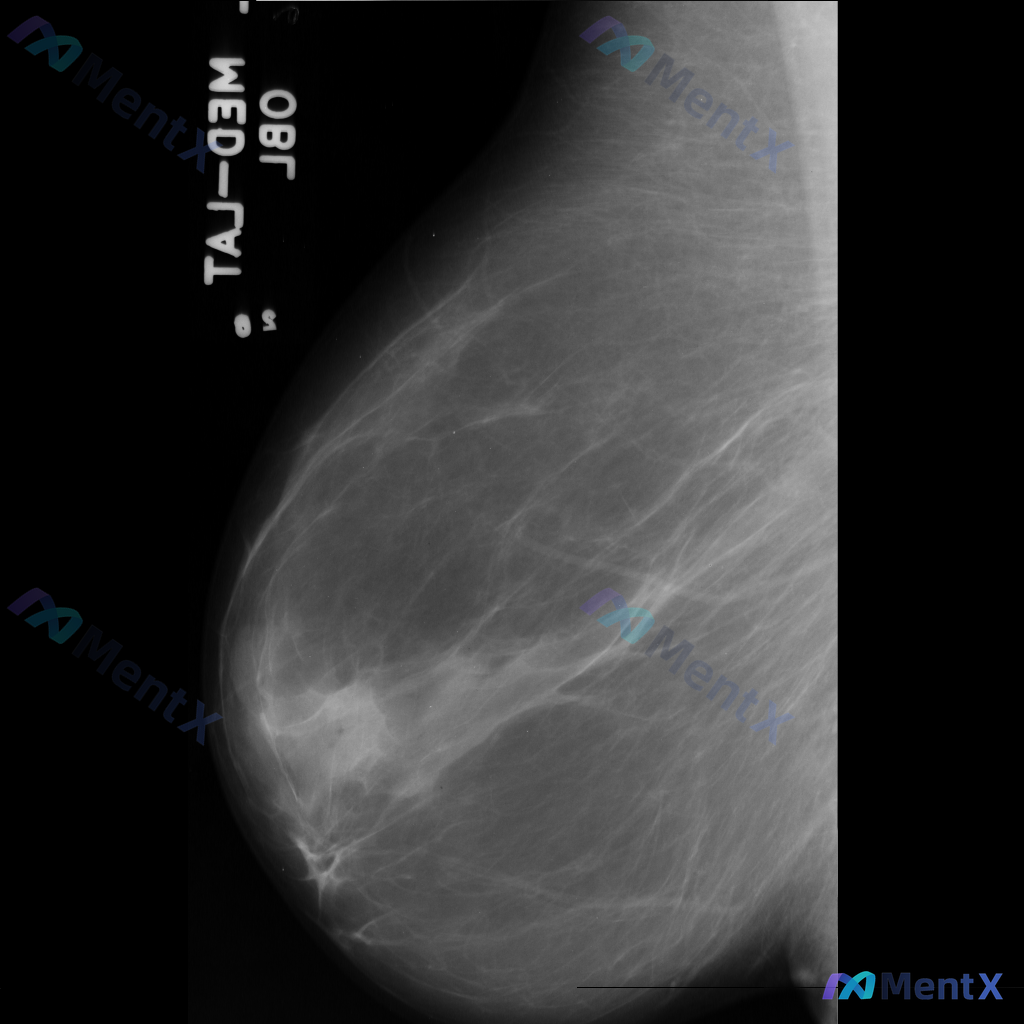

整理到一份乳腺钼靶影像资料,主要表现如下: - 乳腺中后部可见局灶性结构扭曲 - 无明确的肿块核心 - 周围腺体和脂肪界面被不规则牵拉 目前暂不提供既往影像对比和详细病史(手术史、外伤史、炎症史等)。 这种表现大家会先怎么判断?更倾向于往哪种方向考虑?

整理到一个乳腺钼靶影像的读片病例,影像上的核心表现是:不对称致密影伴结构扭曲,暂时没有看到明确的肿块描述,也未提及微钙化、脂肪影等明确良性特征。 这种表现放在一起,大家第一反应会先往哪类情况考虑?或者说,你会更优先关注哪种可能性?